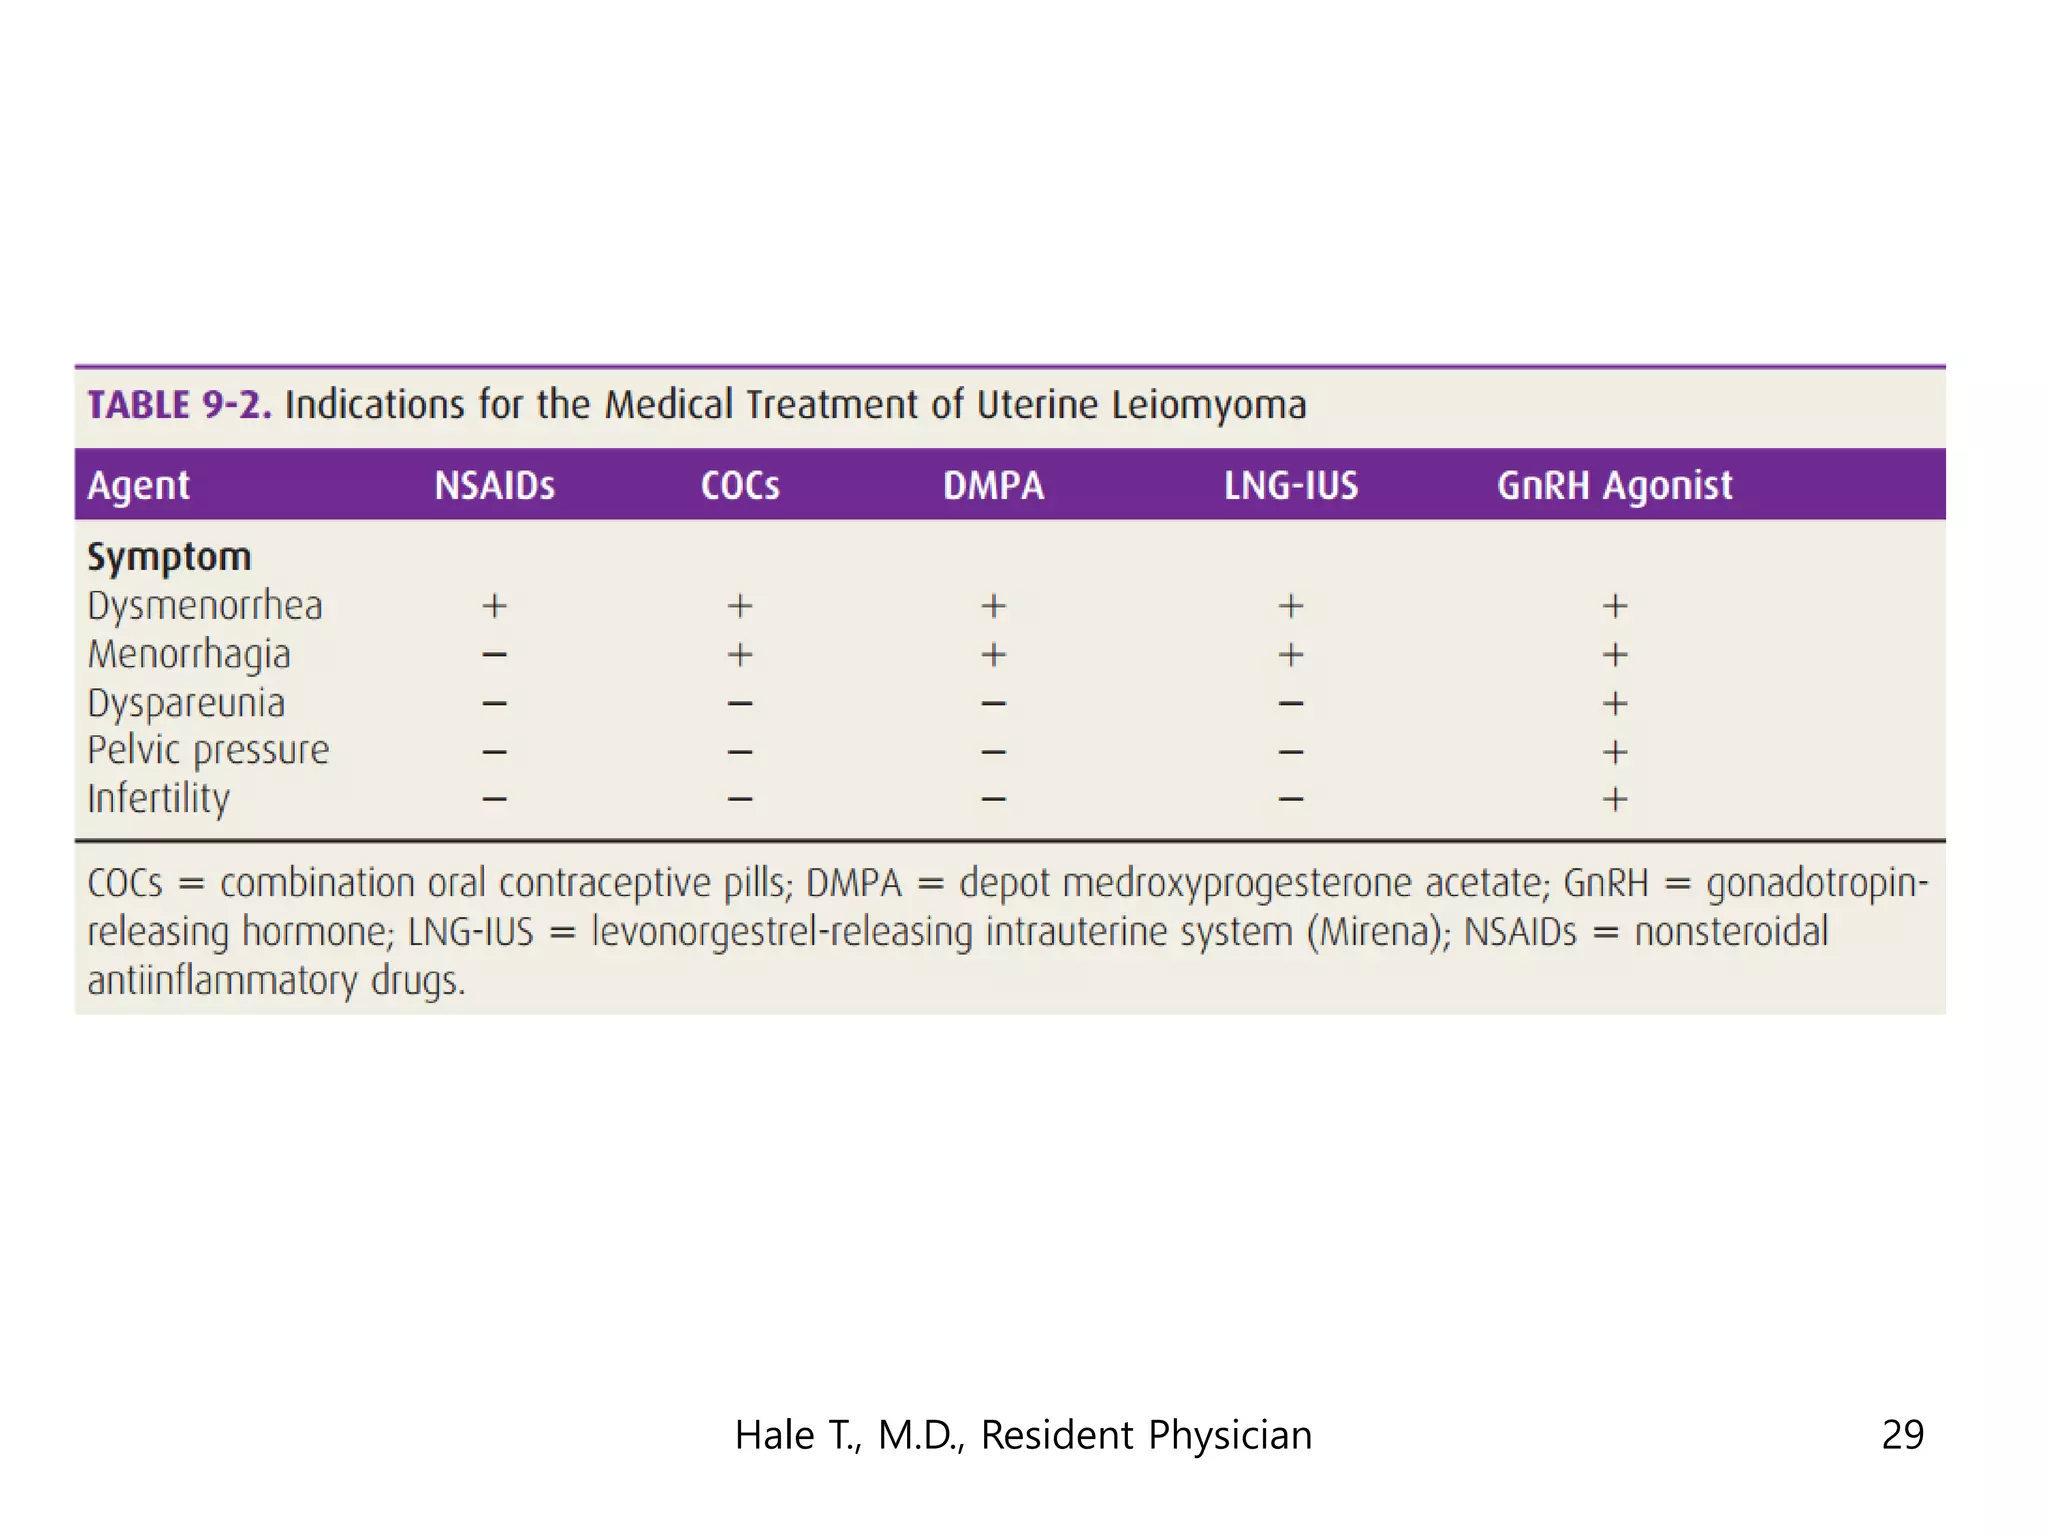

This document discusses myomas (uterine fibroids). It notes that myomas are benign smooth muscle tumors that originate in the uterus and are sensitive to estrogen and progesterone. Symptoms can include bleeding, pain, pressure, and infertility. Diagnosis is usually made through imaging like ultrasound or MRI. Treatment options include observation, drug therapy, uterine artery embolization, or surgical removal of the fibroids. The document also discusses complications that can arise if fibroids are present during pregnancy, such as pain, bleeding, preterm birth, and pregnancy loss.